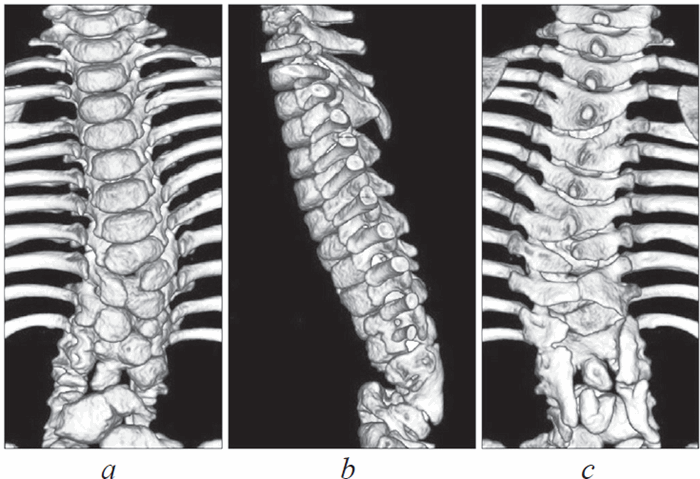

Рис. 1. Предоперационная компьютерная томография: a — множественные дефекты формирования, слияния и сегментации тел позвонков (вид спереди); b — полный поперечный дефект передних структур на уровне условной середины поясничного отдела (вид слева); c — расщепление задних структур нижнегрудного и поясничного отделов (вид сзади)

При контрольной компьютерной томографии через 18 месяцев выявлено приживление трансплантата и формирование сплошного костного блока в зоне вмешательства, обеспечивающее стабильность поясничного отдела позвоночника и низкий потенциал прогрессии кифоза (рис. 3). С точки зрения неврологического дефицита отмечено некоторое улучшение с сохранением нижнего парапареза (больше справа; Frankel D). По данным магнитно-резонансной томографии через 25 месяцев после операции признаков компрессии невральных структур не получено. Оперативное лечение, в том числе декомпрессия и/или мобилизация спинного мозга, в настоящее время не показано. Вместе с тем, учитывая возраст ребенка (5 лет) и потенциал роста, необходимы медицинское сопровождение и регулярные контрольные неврологические и лучевые обследования до окончания костного роста.

Рис. 3. Компьютерная томография через 18 месяцев после операции. Сформирован костный блок в зоне оперативного вмешательства: a — вид спереди; b — вид слева